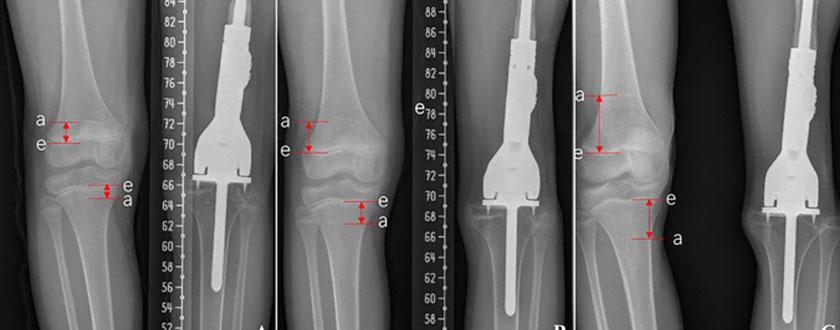

Limb-salvage surgery helps preserve the limb by removing the part of the bone involved with the tumor and some of the tissues that surround it. The bone is replaced with an implant, which can be either a bone graft or a metal prosthesis.

Limb-salvage surgery is part of the treatment for osteosarcoma or Ewing sarcoma. The goal of limb-salvage surgery is to preserve as much of the limb as possible. However, the arm or leg will never be as strong as it was before surgery. Children who have this surgery will not be able to participate in high-impact sports using the affected limb.

There are three main categories of implants used as part of limb-salvage surgery: